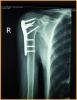

行肱骨近端锁定型钉板(PHILOS)固定术,手术过程:采用全麻或斜方肌阻滞麻醉,用沙滩椅体位,术中肱骨头复位后,用二至三枚克氏针临时固定保持复位,并使其余骨折块复位,然后透视确认复位质量。用5号不可吸收缝线将大小结节缝合修复,再选用适当长度的锁定钉板置于肱骨近端和肱骨干的外侧面。注意避免将钢板放置的过高以致成角螺钉的位置不合适而不能达到最佳骨接触。可用一枚非锁定螺钉固定于肱骨干上可使钢板远近端滑动调整位置。然后使用导向器上锁定螺钉使钢板和螺钉一体化。固定完成后再次透视确认无误,处理好软组织后逐层关闭切口。